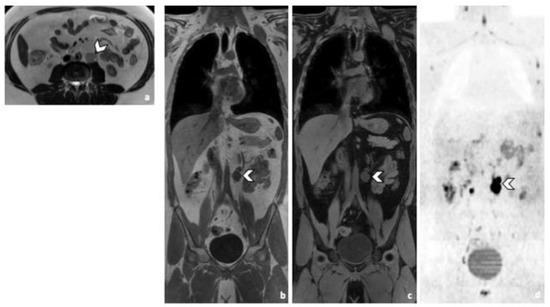

3.3.3. Other Metastatic Lesions

Predictive accuracy of CT was 98%. Accuracy of MRI was 95%, regardless of the WB-MRI protocol. No variation in accuracy was observed between readers. One patient with lung metastasis was missed during CT readings, while two were missed during WB-MRI readings by both readers, regardless of the protocol. The patients that were missed during the WB-MRI readings, had nodules that measured less than 10 mm in their largest diameter. The nodules disappeared after systematic treatment. Practically, if only WB-MRI was used, 2 patients with pulmonary metastasis would have been missed, keeping in mind that the sequences in our protocol were not developed for lung imaging (Figure 5).

Figure 5.

45-year-old man with seminoma. Axial CT image (a) and T2-weighted (b), 3D T1 GRE Fat-Sat (c) and high b-value DWI (b = 1000 s/mm2) (d) MR images. Left pulmonary nodule (arrowhead) detected by both readers during CT and MRI readings. Abbreviations: 3D: Three Dimensional, T1 GRE: T1 Gradient Echo, DWI: Diffusion Weighted Imaging, MRI: Magnetic Resonance Imaging, CT: Computed Tomography.

During the WB-MRI readings both readers missed a patient with a pulmonary granuloma and emphysema and a patient with a Port-a-Cath thrombosis. No other significant findings were missed during the WB-MRI images.